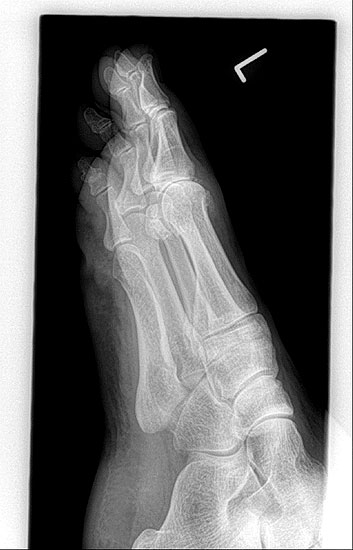

• Röntgenaufnahmen des Vorfußes (unter Belastung) im dorsoplantaren und seitlichen Strahlengang (Abb. 1a+b)

Eine übermäßige Dorsalextension führt neben Druckstellen im Schuhwerk vor allem zu einer mangelnden Lastaufnahme und zur kompensatorischen Hyperflexion im Endgelenk. Sekundäre Metatarsalgien am 1. und 2. Strahl können auftreten. Bei zu starker Plantarflexion ist das Abrollverhalten gestört und das Endgelenk wird durch Hyperextension stark belastet, dies kann zu sekundärer Arthroseentwicklung im IP-Gelenk führen. Seltener sind relevante Rotationsfehlstellungen oder Abweichungen in der Frontalebene mit Valgus- oder Varusstellung. Sofern Schuhzurichtungen und Einlagenversorgungen nicht zur Besserung der Beschwerden führen, ist die operative Stellungskorrektur erforderlich.